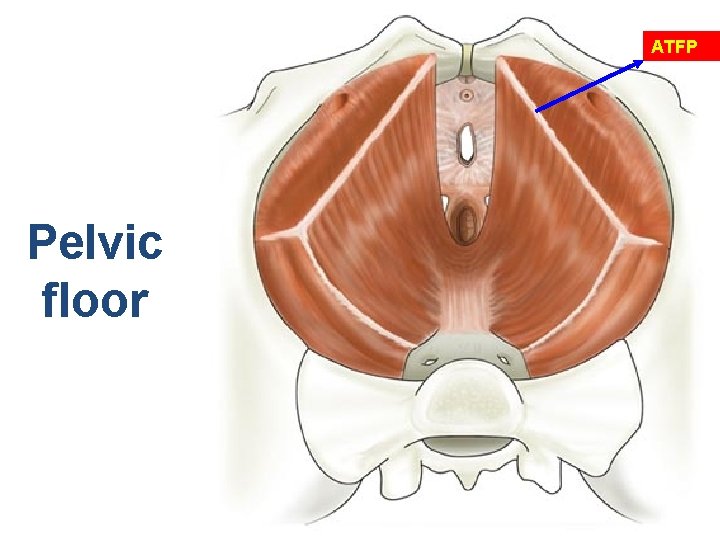

Pelvic Floor Muscles Levator Ani • Puborectalis • Pubococcygeus • Ileococcygeus Obturator Internus Piriformis Coccygeus Levator Plate Netter F Atlas of Human Anatomy Novartis 1997

“Ligaments and Fascia” Cardinal/Uterosacral Complex (Delancy level I) Paracervical Ring Arcus Tendineus Fascia Pelvis ATFP Pubocervical “fascia” Rectovaginal “fascia”

ATFP Pelvic floor